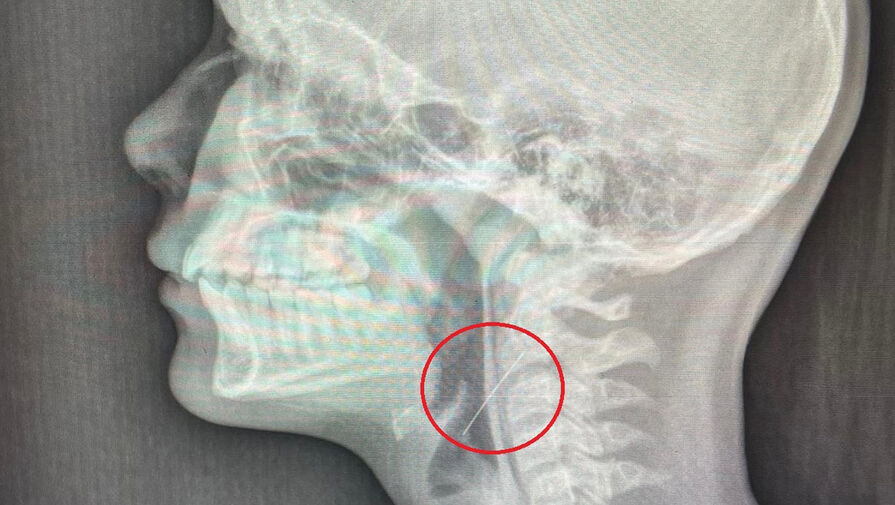

Школьница проглотила иголку, когда вешала на елку гирлянду. В Воронеже девочка украшала дом к Новому году и попала в больницу, ребенок случайно проглотил иглу. Об этом сообщает Минздрав Воронежской области на официальной странице во "ВКонтакте". Девочка-подросток наряжала дома елку, ...